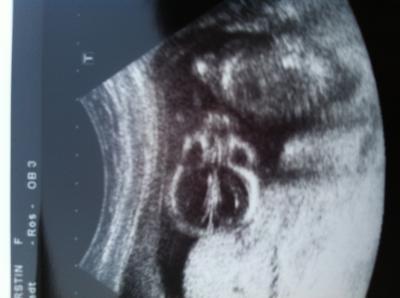

Guten morgen ihr lieben! Beim FA gestern war alles super, dem Zwerg geht es gut und ist die ganze Zeit nur rumgeturnt. Hat zwischendurch sich an den Kopf gelangt, wie wenn es uns schon den Vogel zeigen will, dann hat es ganz elegant die Beinchen überschlagen. War total süß, wiegt jetzt ca 148g und ist zeitgerecht entwickelt, das Gerät meintee den 1.12. als ET, aber die FÄ meinte wegen den paar Tagen, da ändert sie nichts. Achso, ein vorsichtiges Outing gab es auch....sie meinte sie sieht da was zwischen den Beinchen, warte aber mit dem shoppen doch noch den 3D Ultraschall ab, weil ganz sicher war sie sich nicht. Meine Tochter war wieder beim Baby TV dabei, als wir aus der Praxis raus sind, brach sie total in Tränen aus , sie wünschte sich so sehr ein Mädchen. Hab ihr dann gesagt, das es doch wichtiger ist, das unser Zwerg gesund ist. Bildchen häng ich noch hinten dran. Wünsch euch noch nen schönen nicht allzuheißen Tag! Lg Kerstin

Bild zu FA Bericht von gestern... - Forum für November - Mamis